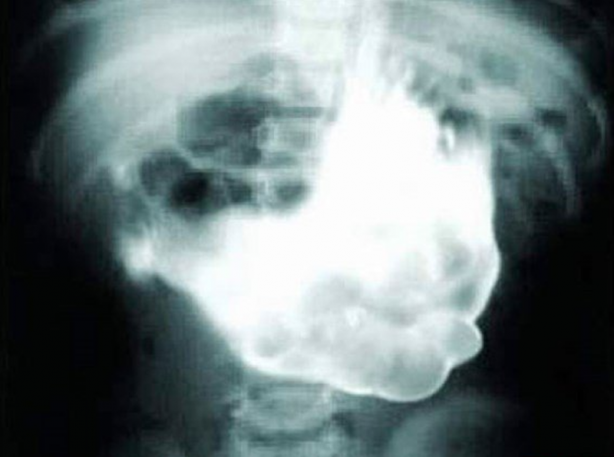

Yemek yedikten hemen sonra röntgen filmi çekilen yılan.